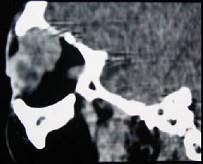

问题 女,36岁,左眼眶外上部可触及一无痛性包块有两年,眼球向内下方突出,CT检查如图,最可能诊断为 ( )

选项 A、淋巴瘤 B、淋巴瘤样增生 C、泪腺恶性上皮性肿瘤 D、炎性假瘤 E、泪腺良性混合瘤

答案 E